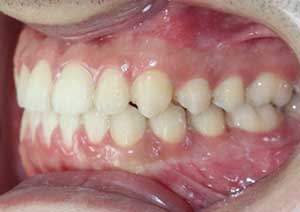

Le cross-bite antérieur (ou articulé croisé antérieur) est une anomalie d’occlusion dans laquelle une ou plusieurs dents du maxillaire se retrouvent en arrière des dents mandibulaires, alors qu’elles devraient être en avant.

Traitement : Dans ce cas, nous avons eu recours à la mise en place de cales postérieures en résine bleue au niveau des premières molaires maxillaires, Elles ont permis de séparer temporairement les mâchoires afin de laisser les dents du haut se replacer correctement devant celles du bas, corrigeant ainsi le cross-bite antérieur.

Par la suite, ces cales ont été déplacées sur les faces palatines des incisives maxillaires dans le but d’optimiser l’articulé postérieur, notamment au niveau des molaires droites, qui présentaient également un articulé inversé.